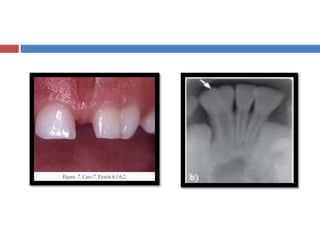

 Se presenta cuando el germen de un diente intenta dividirse.

 Es una estructura dentaria, con dos coronas que tiene una sola

raíz y un solo conducto radicular.

 Radiográficamente se observan dos coronas conformadas con

un canal radicular.

 Etiología hereditaria